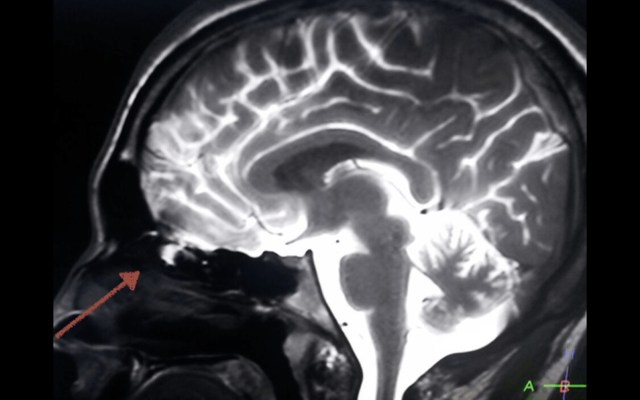

• HIDROCEFALIA

HIDROCEFALIA

Edouard Busch, y el noruego Arn Torkildsen con sus aportaciones técnicas al tratamiento de la hidrocefalia no comunicante.

• Válvulas para tratar la hidrocefalia. Derivaciones

Válvulas para tratar la hidrocefalia. Derivaciones

El colombiano Salomón Hakim, descubre la hidrocefalia normotensiva y desarrolla la válvula unidireccional para tratarla, la cual puede regular la presión, a diferencia de las válvulas ya creadas de Holter y Spitz en eso de los años 50